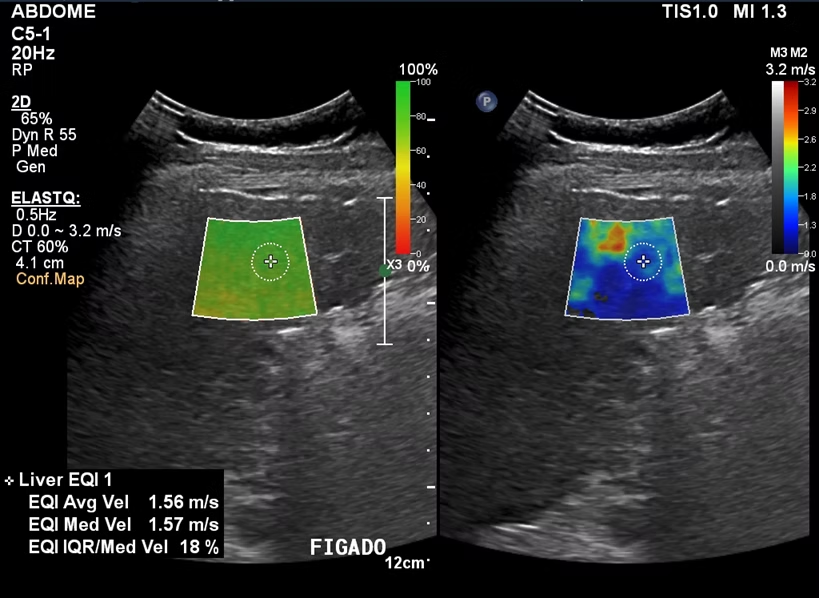

A prevenção do câncer de fígado é ,muito importante, especialmente nos casos em que a cirrose hepática é um fator de risco. Por esse motivo, pacientes com cirrose devem realizar Ultrassom de abdômen a cada 6 meses para identificar possíveis nódulos em fases iniciais, quando podem ser tratados e curados. A detecção precoce pode aumentar as chances de um tratamento bem-sucedido e melhores resultados para os pacientes com câncer de fígado.